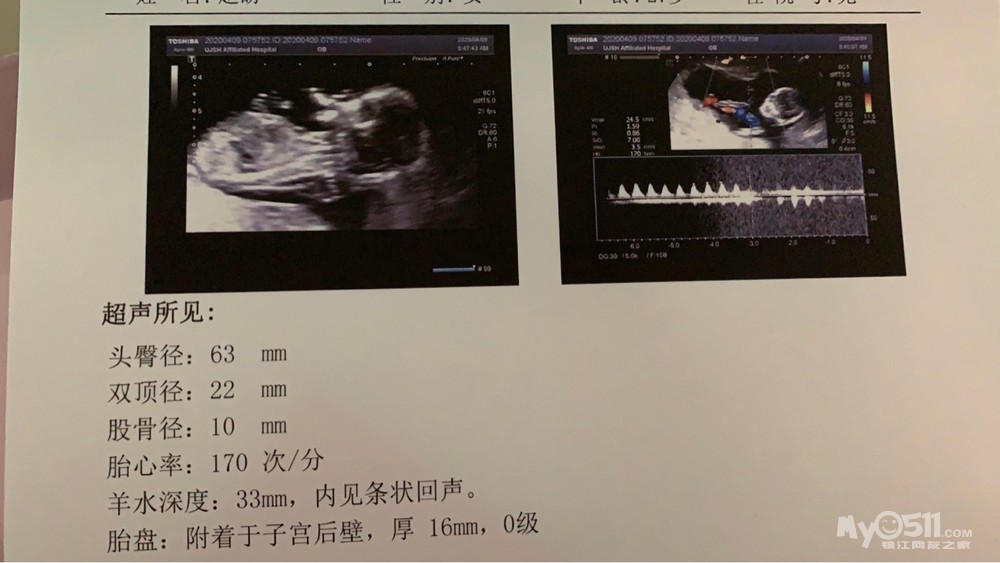

好孕证明: